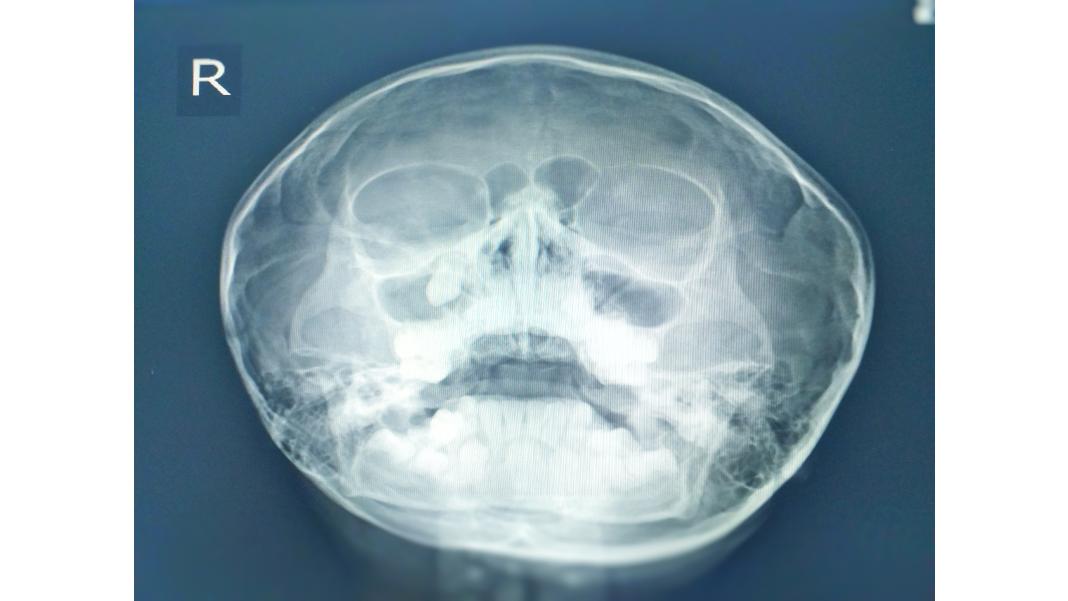

1. Antiinflamator: Serrapeptaza este cunoscută pentru proprietățile sale antiinflamatorii, fiind folosită pentru a reduce umflăturile și durerea asociată cu inflamațiile. Serrapeptaza este deosebit de eficientă în ameliorarea inflamațiilor cronice din sfera ORL. Este benefică în dificultățile de înghițire, disfonie și obstrucție nazală. Studiile au evidențiat și efecte salutare în normalizarea secrețiilor bronhopulmonare. Ameliorează dureri de orice natură, datorate unor afecțiuni precum sinuzită, rinită, migrene, dureri de dinți, osteoartrită, artrită reumatoidă, răni, traume post-operatorii, cancer pulmonar, emfizem pulmonar.

4. Sprijin pentru sănătatea respiratorie: Aceasta poate ajuta la subțierea și eliminarea mucusului, făcând-o utilă în tratarea unor afecțiuni respiratorii, cum ar fi sinuzita sau bronșita cronică.